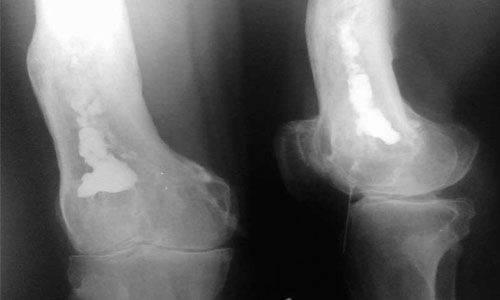

Рентгенография является подспорьем только после двух недель болезни. В зоне воспаления просматривается разрежение ткани, нечеткость костных контуров. Характерен линейный периостит – нечеткая тень, параллельная поверхности кости. Затем начинается некроз костной ткани с образованием секвестров.

Постепенно на снимках становится очевидным склерозирование, остеопороз и проявления периостита. Это говорит об уменьшении остроты и хронизации процесса.

Для уточнения диагноза применяется изотопное сканирование, компьютерная и магнитно–резонансная томография.